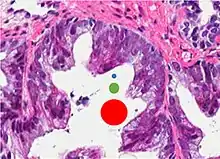

| Acinar adenocarcinoma - 93%[2] | Adenocarcinoma (not otherwise specified/ conventional/ usual acinar)[3] |

77%[notes 2] | 54%[notes 2] | ![]() |

Microscopic characteristics

- Specific but relatively rare

- [notes 4]

- Collagenous micronodules[4]

- Glomerulations,[4] epithelial proliferations into one or more gland lumina, typically a cribriform tuft with a single attachment to the gland wall.[18]

- Perineural invasion.[4] It should be circumferential[18][notes 5]

- Angiolymphatic invasion[4]

- Extraprostatic extension [4]

Glomerulation.

- Relatively common and highly specific

- [4]

- Multiple nucleoli

- Eccentric nucleoli[4]

Acinar adenocarcinoma with multiple nucleoli.

Acinar adenocarcinoma with double and eccentric nucleoli.

- Less specific findings.

- Mitoses (also seen in for example high-grade prostatic intraepithelial neoplasia (HGPIN) and prostate inflammation).[4]

- Prominent nucleoli[4]

- Intraluminal eosinophilic secretion[4]

- Intraluminal blue mucin[4]

Adenocarcinoma with two mitoses in reactive epithelium.

Acinar adenocarcinoma with intraluminal blue mucin.

In uncertain cases, a diagnosis of malignancy can be discarded by immunohistochemical detection of basal cells.[4]